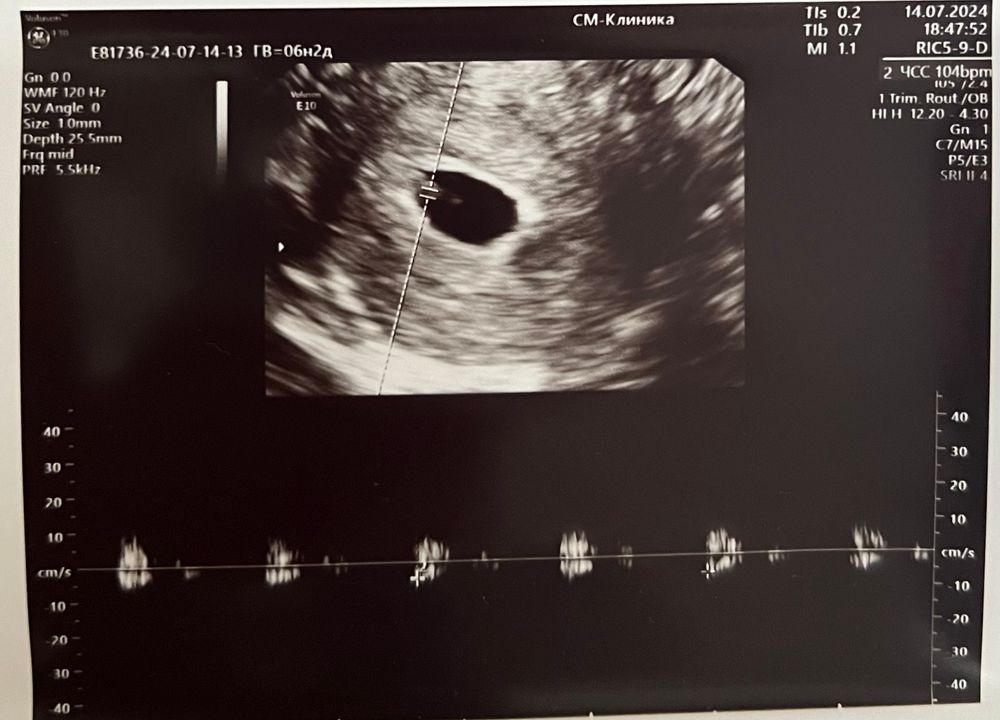

25дпп. Услышали сердечко 🥹🥰

14.07.2024